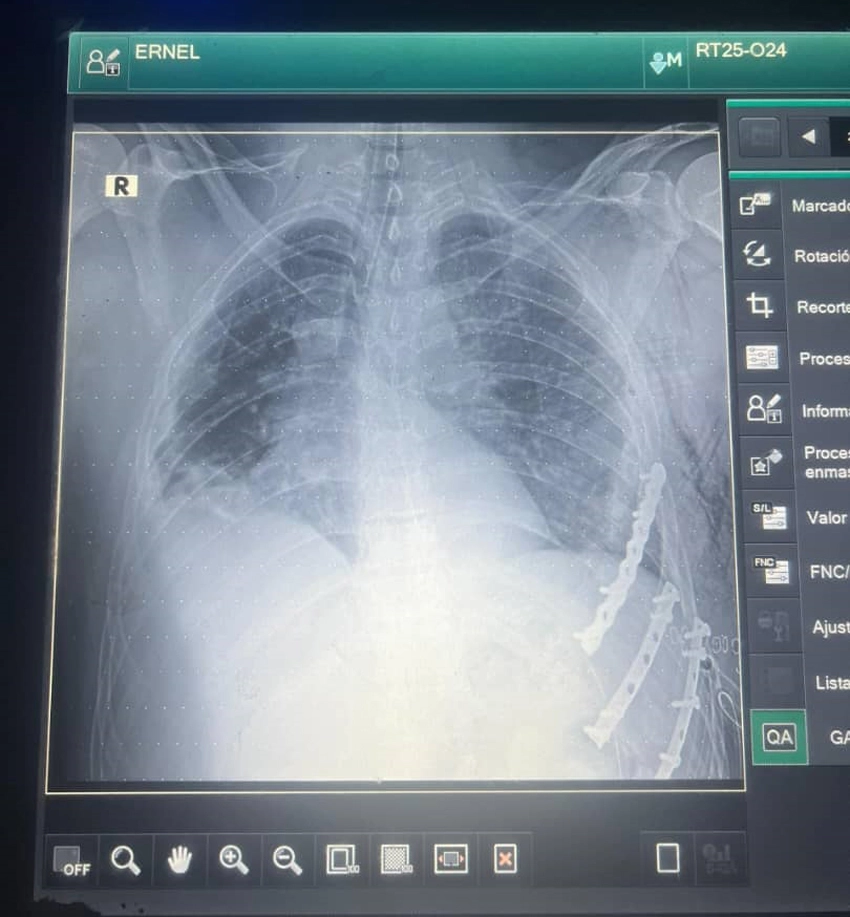

La rápida y efectiva respuesta ante una emergencia de esta naturaleza fue esencial para salvar la vida de Ernel Sánchez González, quien según comenta el también especialista de segundo grado en Medicina General Integral (MGI) llegó con buena hemodinamia, se le realizaron exámenes complementarios correspondientes de rayos X y ultrasonografía que evidenciaron la necesidad de la intervención.

«Con la apertura del tórax se identificaron las costillas, fue preciso abrir el hemitórax izquierdo debido a que el paciente tenía un hemotórax de 1200 ml aproximadamente de sangre. Se controló el sangrado y tras comprobar que no había ninguna repercusión hemodinámica, ni riesgo de sangrado realizan la afinación de la pared torácica y osteosíntesis. Fue una cirugía compleja, de más de dos horas donde debimos trabajar con la mayor seguridad y conocimiento posible para que el paciente pudiera recuperarse», significó el también profesor asistente.